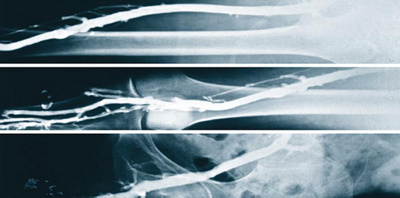

Abb. 1

Schema Kombinationstherapie: Ober- und Unterschenkel sind durch eine Manschette vom Kreislauf ausgeschaltet. Am Unterschenkel findet eine hochdosierte chemische Thrombenauflösung statt. Im Becken rechts im Bild werden die Thromben mechanisch mit dem Ballonkatheter entfernt.